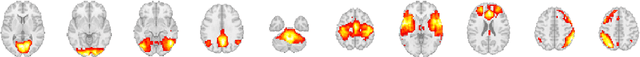

Abstract:Using deep learning models to recognize functional brain networks (FBNs) in functional magnetic resonance imaging (fMRI) has been attracting increasing interest recently. However, most existing work focuses on detecting static FBNs from entire fMRI signals, such as correlation-based functional connectivity. Sliding-window is a widely used strategy to capture the dynamics of FBNs, but it is still limited in representing intrinsic functional interactive dynamics at each time step. And the number of FBNs usually need to be set manually. More over, due to the complexity of dynamic interactions in brain, traditional linear and shallow models are insufficient in identifying complex and spatially overlapped FBNs across each time step. In this paper, we propose a novel Spatial and Channel-wise Attention Autoencoder (SCAAE) for discovering FBNs dynamically. The core idea of SCAAE is to apply attention mechanism to FBNs construction. Specifically, we designed two attention modules: 1) spatial-wise attention (SA) module to discover FBNs in the spatial domain and 2) a channel-wise attention (CA) module to weigh the channels for selecting the FBNs automatically. We evaluated our approach on ADHD200 dataset and our results indicate that the proposed SCAAE method can effectively recover the dynamic changes of the FBNs at each fMRI time step, without using sliding windows. More importantly, our proposed hybrid attention modules (SA and CA) do not enforce assumptions of linearity and independence as previous methods, and thus provide a novel approach to better understanding dynamic functional brain networks.